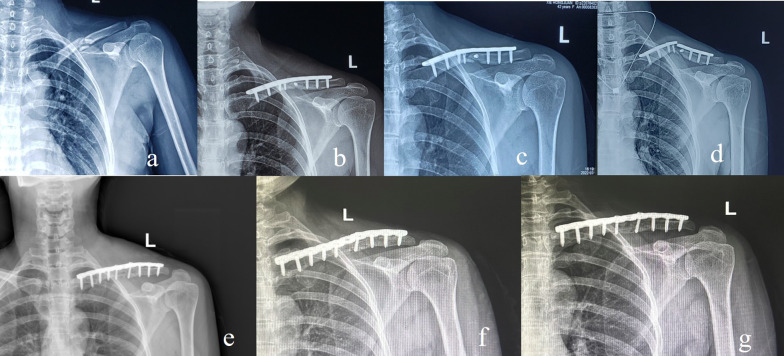

Background: Open reduction, superior plate (SP) fixation, and autologous cancellous granular bone grafting (ACGBG) are common strategies for treating clavicular midshaft atrophic nonunion (CMAN). We aimed to compare the radiological findings and clinical effects of two autologous cancellous bone grafts (ACBGs) and those of single SP fixation, to treat CMAN.

Methods: This retrospective study comprised 62 patients admitted to our hospital with CMAN (ACGBG with single SP fixation between March 2012 and October 2017, 32 patients; autologous cancellous structured bone grafting [ACSBG] with single SP fixation between November 2017 and May 2021, 30 patients). Patient visual analog scale (VAS) scores for pain and disability of the arm, shoulder, and hand (DASH) scores, obtained preoperatively and at final follow-up, were recorded and analyzed. Statistical differences between the ACGBG and ACSBG groups were assessed using Fisher's exact and two-sample independent t tests.

Results: No statistically significant differences were observed between the two groups in terms of patient demographics or the incidence of complications. VAS and DASH scores decreased significantly from the preoperative day to 9 months postoperatively in both groups, but this difference was not statistically significant at final follow-up. However, at 3 and 6 months postoperatively, compared with mean VAS and DASH scores in the ACGBG group, the ACSBG group showed lower pain and dysfunction scores (p < 0.05). The mean fracture healing times were 15.2 (range, 12-20) and 18.6 (range, 12-32) weeks in the ACSBG and ACGBG groups, respectively (p = 0.01). One case of plate breakage occurred in the ACGBG group at 5 months postoperatively, with recovery following ACSBG revision with single SP fixation.

Conclusions: ACSBG combined with single SP fixation is a promising and effective alternative technique for promoting bone union and postoperative early functional rehabilitation in treating CMAN.